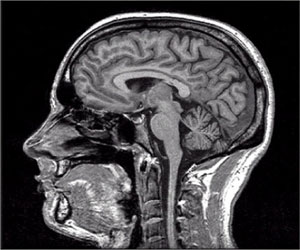

أكد أستاذ الطب النفسي بكلية طب القصر العيني جامعة القاهرة د.سعيد عبدالعظيم أن أخبار العنف والقتل والمظاهرات والأخبار عن وقوع هجوم أو انفجارات وغيره تؤثر سلبا على إشارات المخ للمراكز الجنسية . وأوضح د.سعيد أن هذا ينعكس بشكل مباشر على الرغبة الجنسية لدى الرجال والنساء على حد سواء لان المخ هو المتحكم الرئيسي في العلاقة الجنسية فتستمر العلاقة ضعيفة بسبب التوتر وهذه الظروف غير المريحة. ويقول أن الاكتئاب مرض منتشر ويؤثر على الرغبة الجنسية والرغبات الأساسية مثل الطعام والنوم سواء بالزيادة أو النقصان والشعور بالحزن. وكشف أستاذ أمراض الذكورة ورئس الجمعية العربية للصحة الجنسية د.طارق أنيس أن المعدلات العالمية لاضطراب الانتصاب بين الرجال من جميع الأعمار 18.6% أي أن واحد من كل خمسة رجال تقريبا يعاني من ضعف الانتصاب بينما تبلغ النسبة بين الرجال فوق سن الأربعين 52% . وأضاف أنه رغم عدم توفر إحصائيات قومية عن نسب الإصابة بضعف الانتصاب بين المصريين فان هناك مؤشرات تنبأ بزيادة الإصابة عن المؤشرات العالمية. ونصح د.طارق بعلاج الأمراض المزمنة التي تؤدي إلى ضعف الانتصاب مع تعديل نمط الحياة غير الصحي مثل الإقلاع عن التدخين وعدم إدمان المواد المخدرة والكحوليات وممارسة الرياضة والتخلص من الوزن الزائد والبعد عن الضغوط النفسية وتناول الأطعمة الصحية بالإضافة إلى استخدام مثبطات النوع الخامس من إنزيم فوسفود ايإستريز سواء التي تستعمل عند الحاجة أم ما يستعمل منها بصفة يومية وهي العلاجات التي تعد طفرة حقيقية ليس فقط في وسائل علاج الضعف الجنسي ولكن أيضا في تحسين نوعية الحياة. وأوضح بروفيسور الصحة النفسية والغدد جامعة لاكيلا بايطاليا د.ايمانويل جانيني أن الدراسات الحديثة أثبتت أن عقارات الضعف الجنسي تحسن المريض من الناحية الشخصية والطبية وتؤدي إلى تحسن ملحوظ في الدورة الدموية وتدفق الدم في العضو الذكري. جاء هذا في المؤتمر الصحفي الذي عقدته الجمعية العربية للصحة النفسية الخميس 3 أكتوبر في أحد فنادق القاهرة برعاية شركة فايزر للصناعات الدوائية.